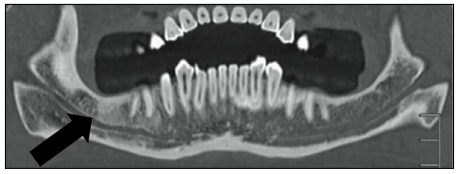

Observe a reconstrução panorâmica da mandíbula por tomografia computadorizada:

Qual é a estrutura anatômica indicada pela seta?